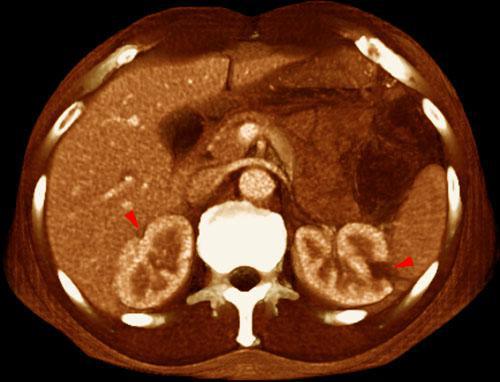

Infartos renales múltiples

VR seccional. Visión axial caudal. TC contrastado en fase venosa. Lesiones hipodensas multifocales bilaterales y periféricas (puntas de flecha) en un paciente con neoplasia broncopulmonar